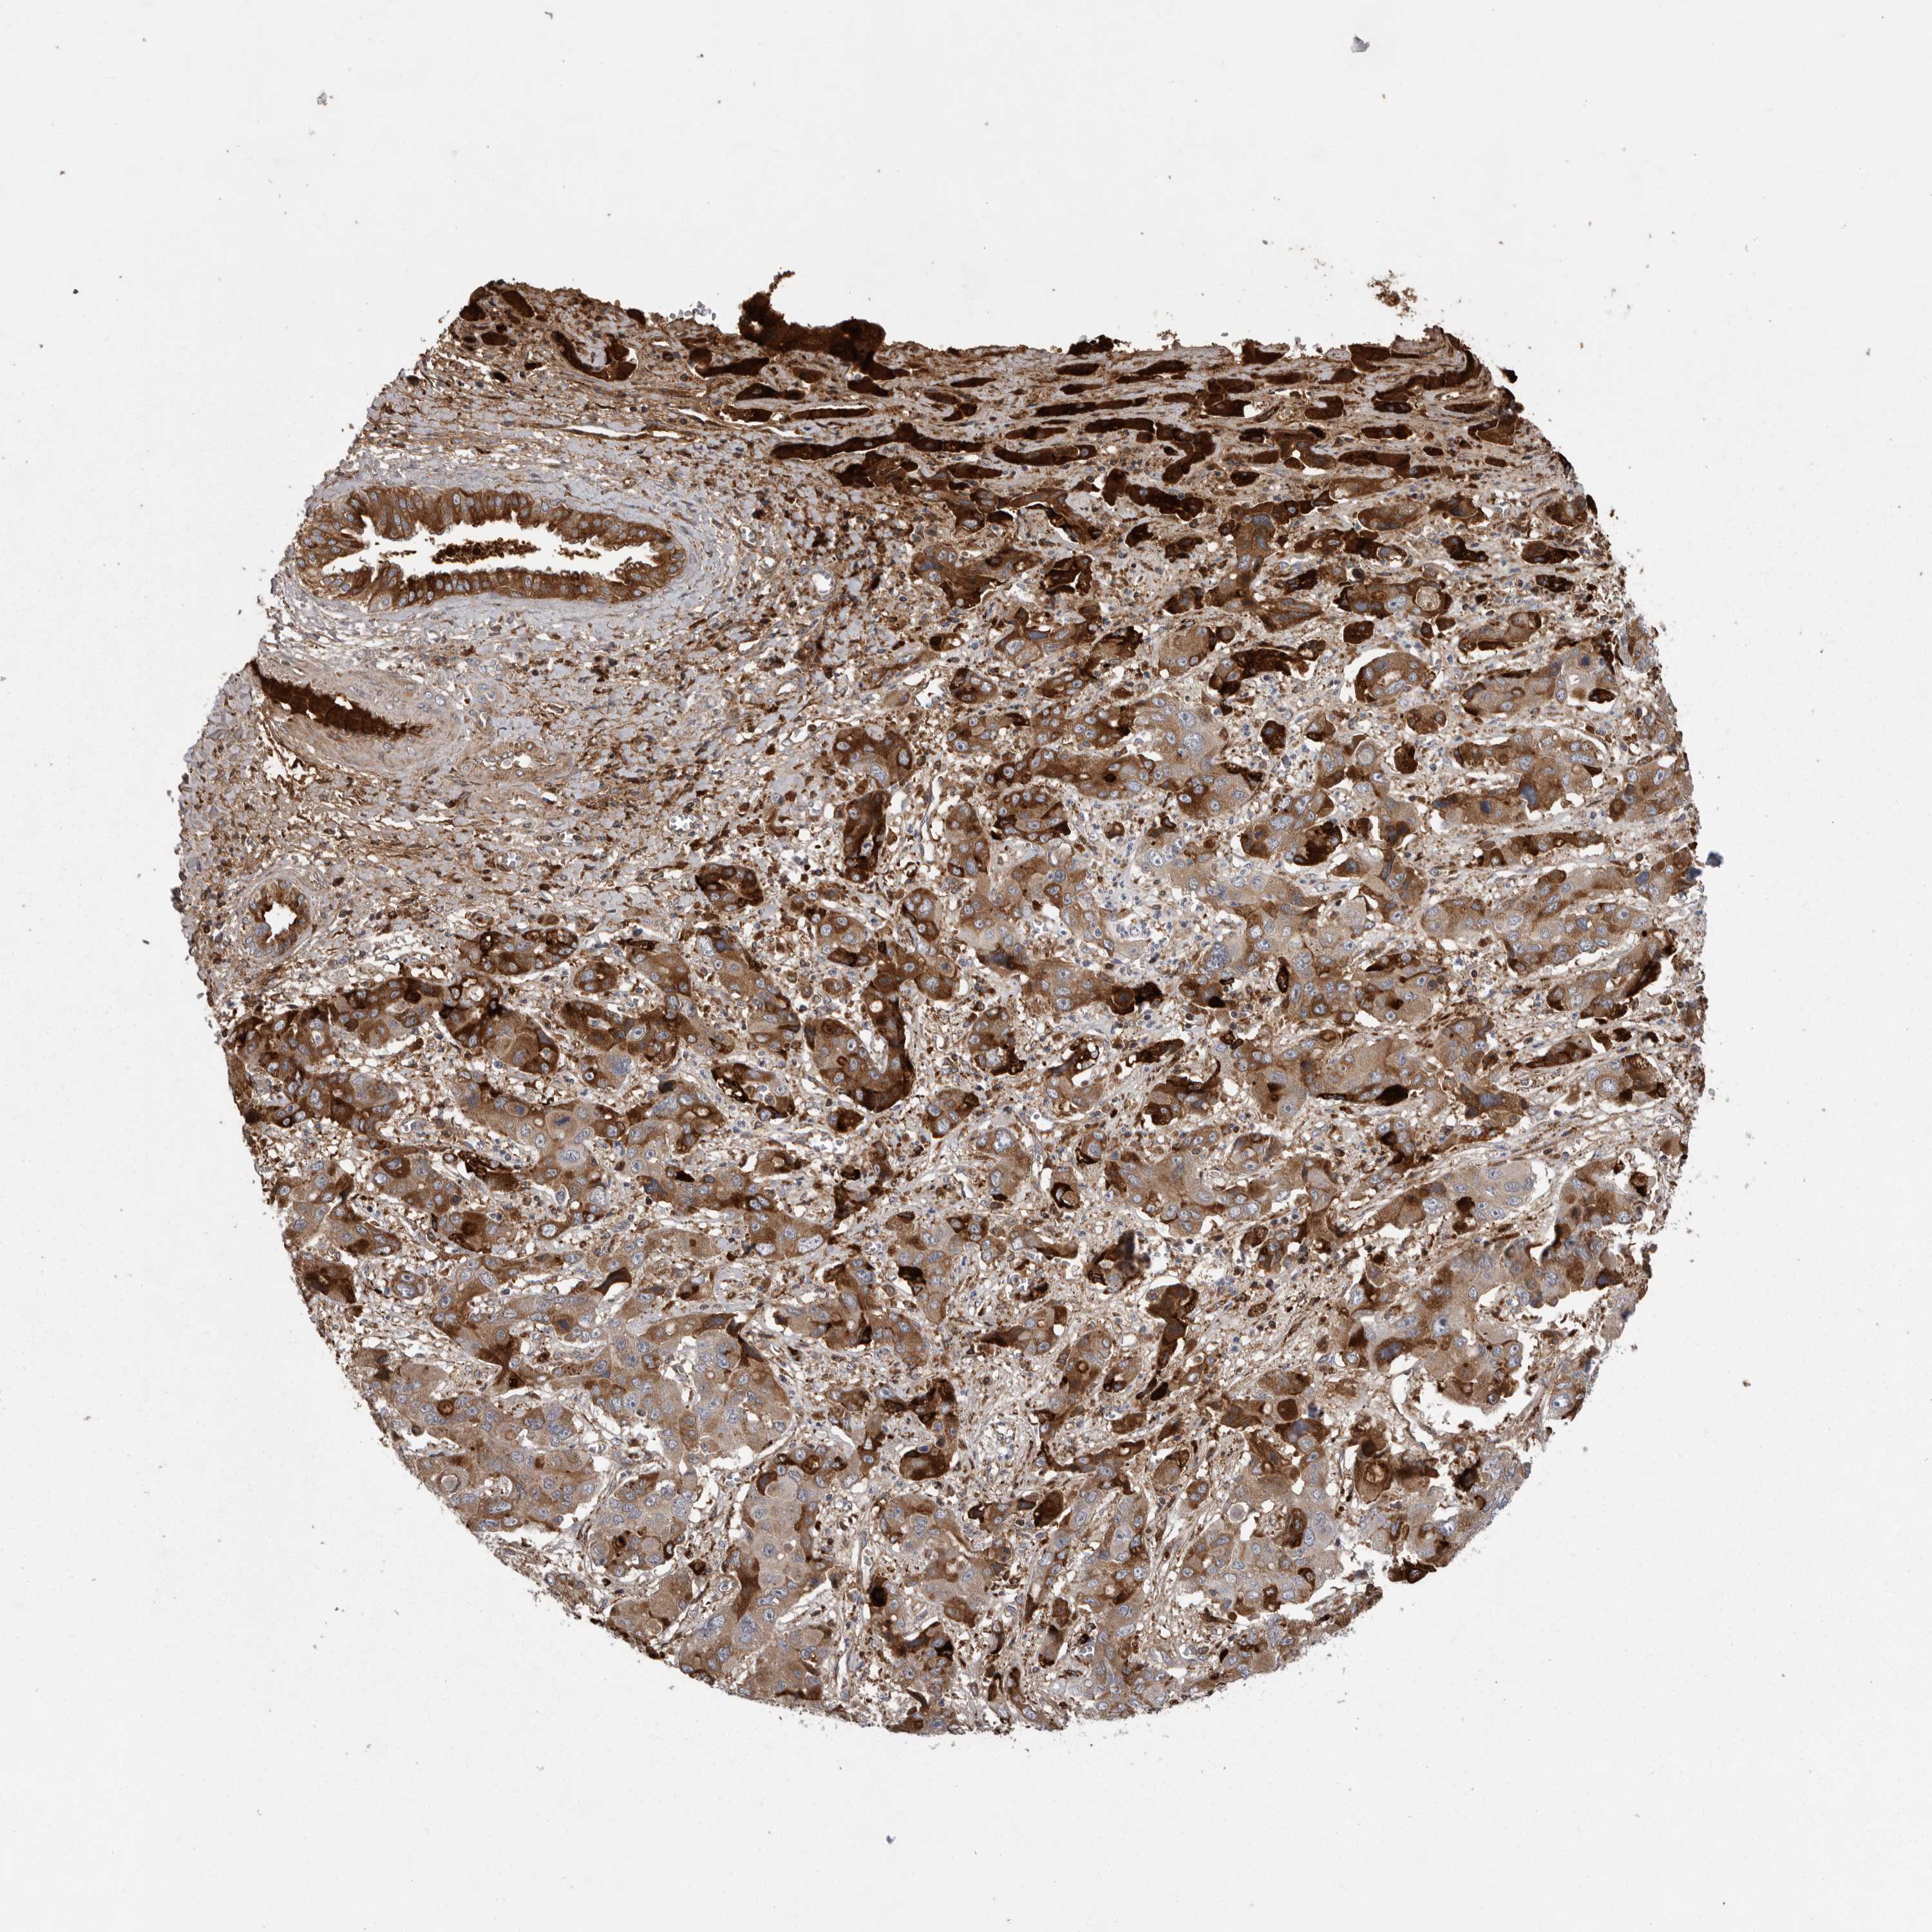

LIVER CANCER - Protein expressioni

A mouse-over function shows sample information and annotation data. Click on an image to view it in a full screen mode. Samples can be filtered based on level of antibody staining by selecting one or several of the following categories: high, medium, low and not detected. The assay and annotation is described here.

Note that samples used for immunohistochemistry by the Human Protein Atlas do not correspond to samples in the TCGA dataset.

Antibody stainingi

Antibody staining in the annotated cell types in the current human tissue is reported as not detected, low, medium, or high, based on conventional immunohistochemistry profiling in selected tissues. This score is based on the combination of the staining intensity and fraction of stained cells.

Each image is clickable and will lead to virtual microscopy that enables deeper exploration of all samples and also displays staining intensity scores, fraction scores and subcellular localization as well as patient and tissue information for each sample.

Antibody HPA027367

Antibody HPA027396

Antibody CAB005036

Staining

High

Medium

Low

Not detected

Intensity

Strong

Moderate

Weak

Negative

Quantity

>75%

75%-25%

<25%

None

Location

Nuclear

Cytoplasmic/membranous

Cytoplasmic/membranous,nuclear

Cholangiocarcinoma

Carcinoma, Hepatocellular, NOS